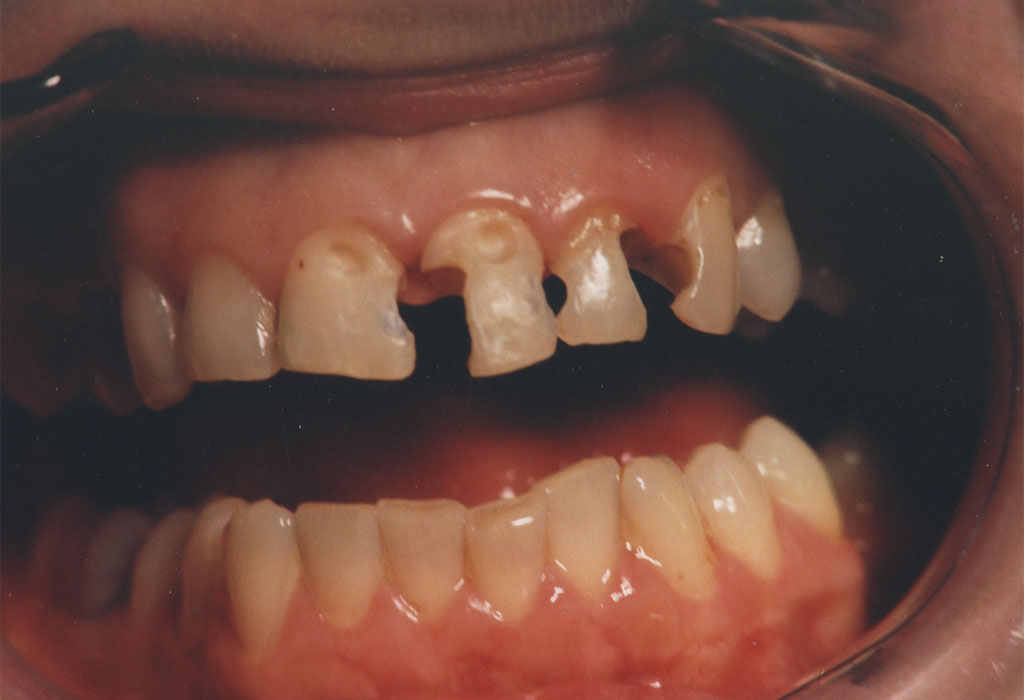

Rekonstrukcijom zuba po boji, obliku i veličini plombe izgledaju potpuno prirodno i traju dugi niz godina.